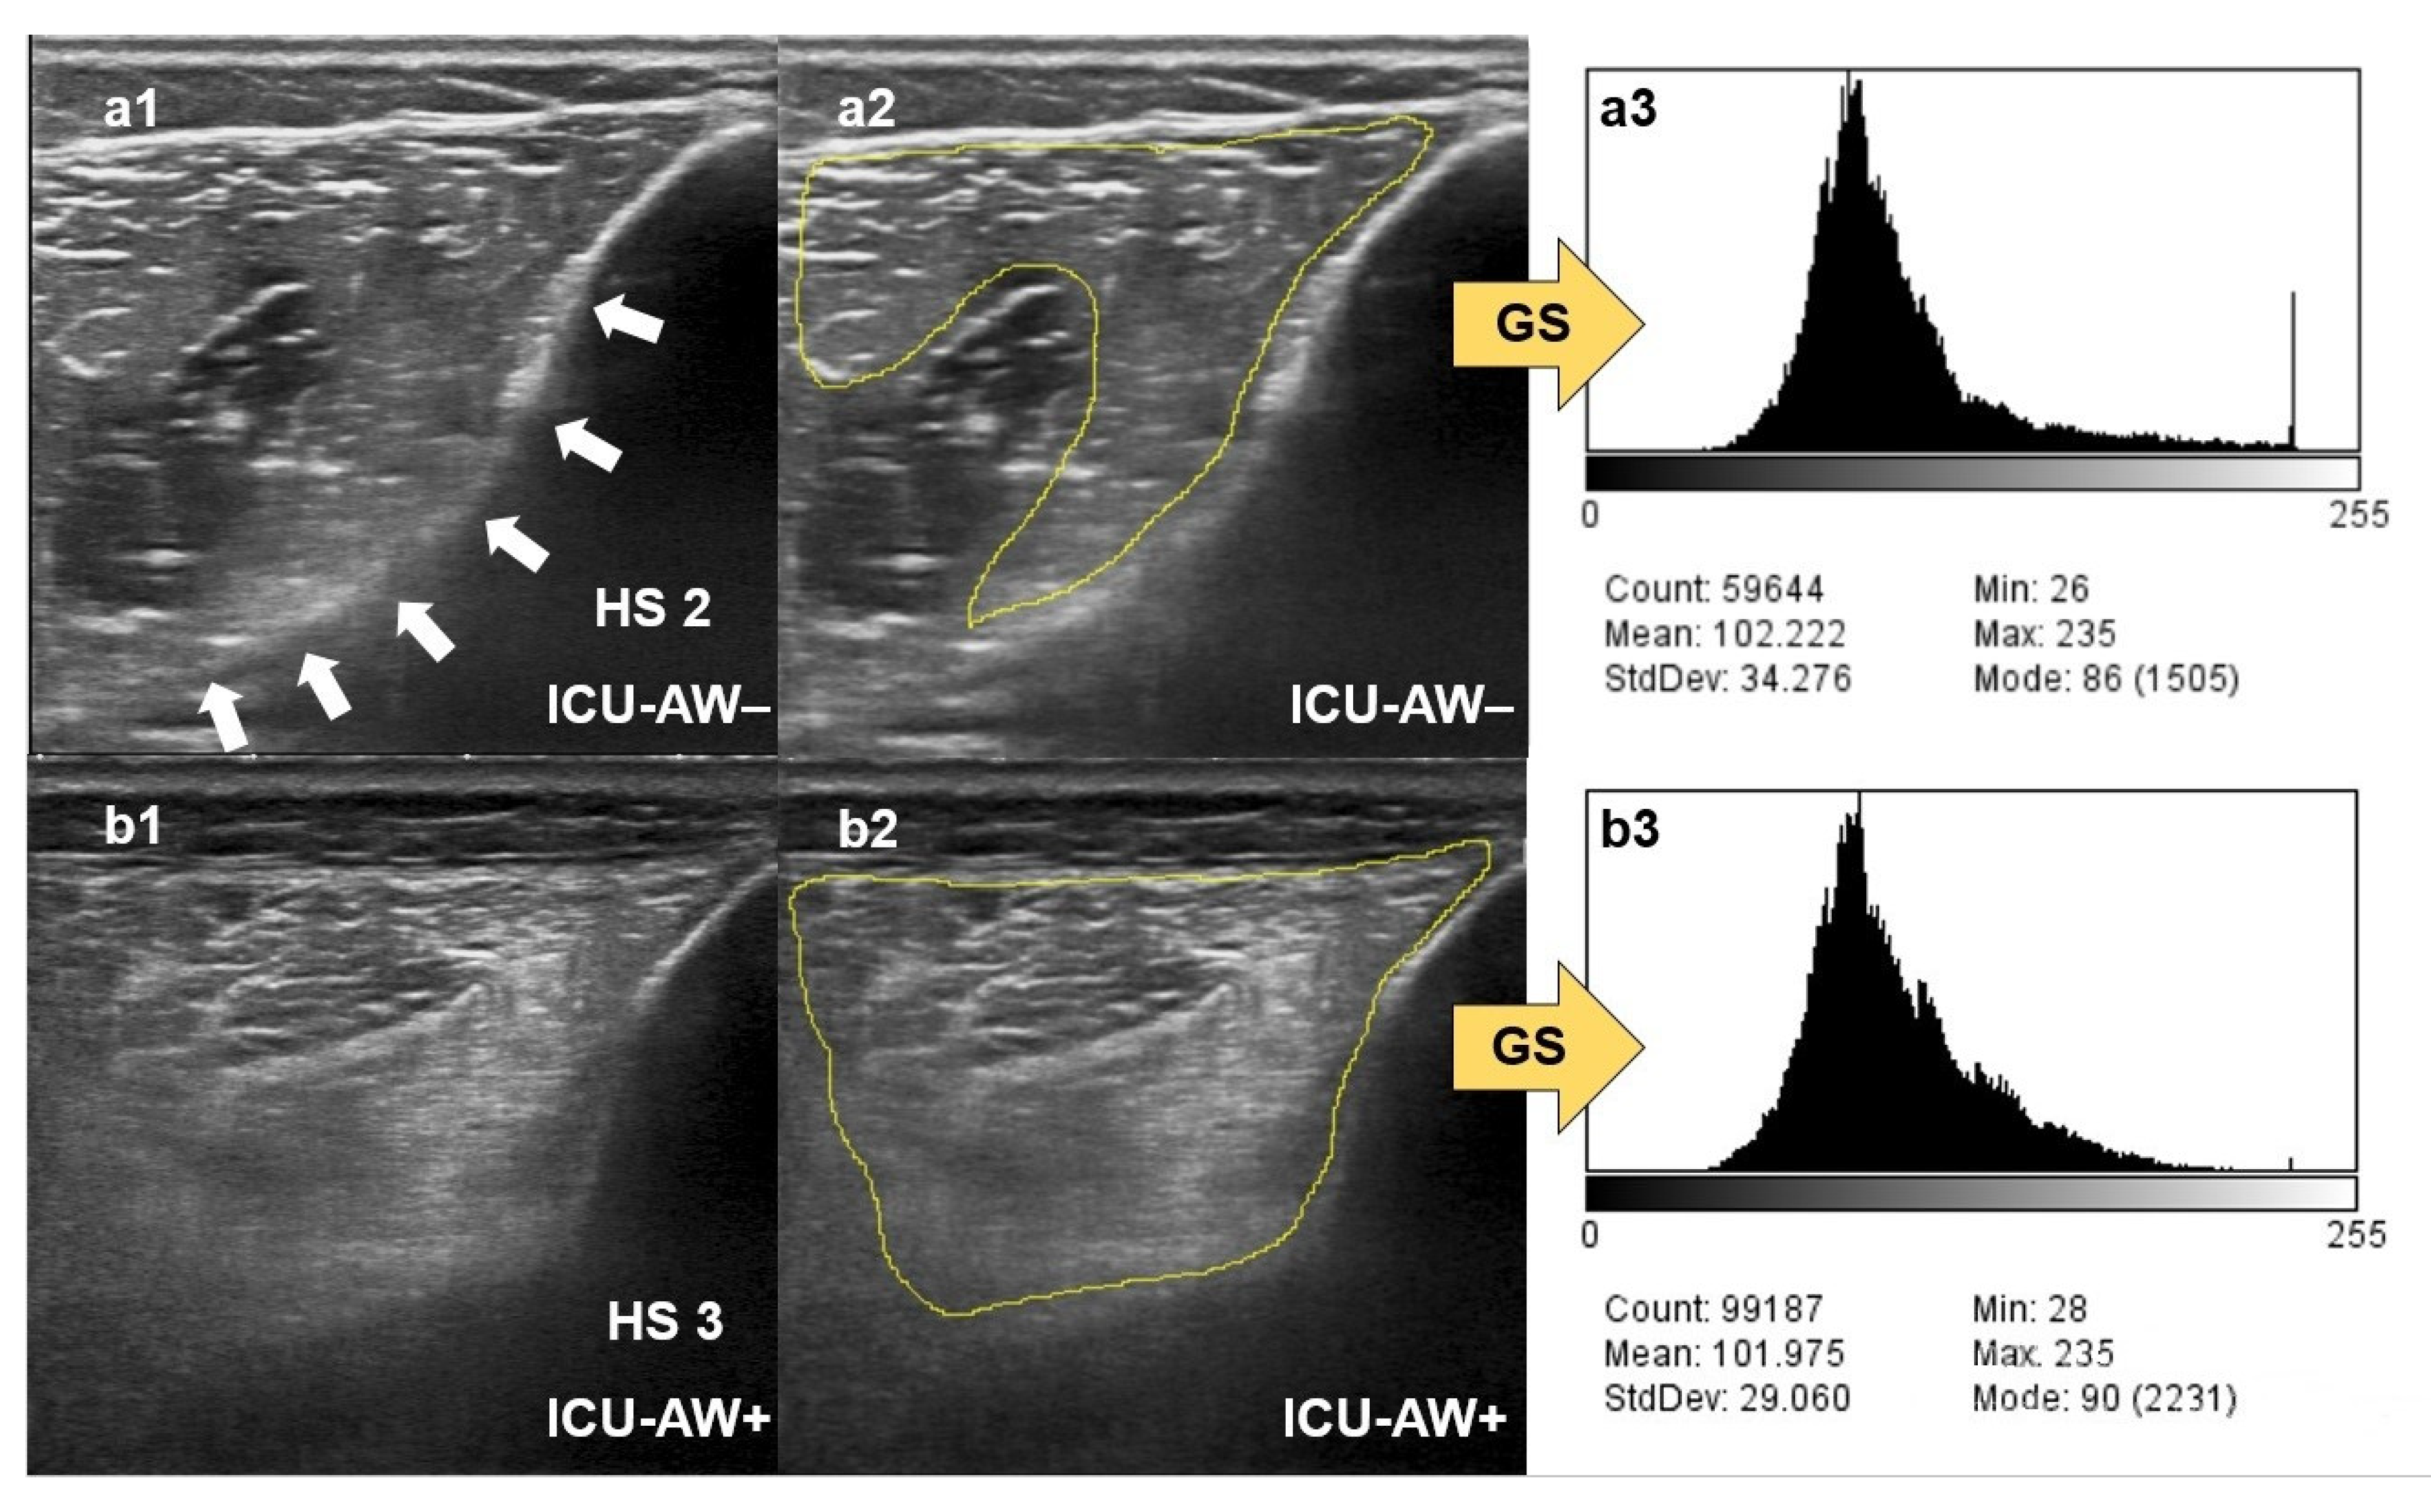

2.4. Qualitative Assessment of Muscle Echogenicity Using the Heckmatt Scale

2.5. Quantitative Greyscale Analysis of Muscle Echogenicity with ImageJ